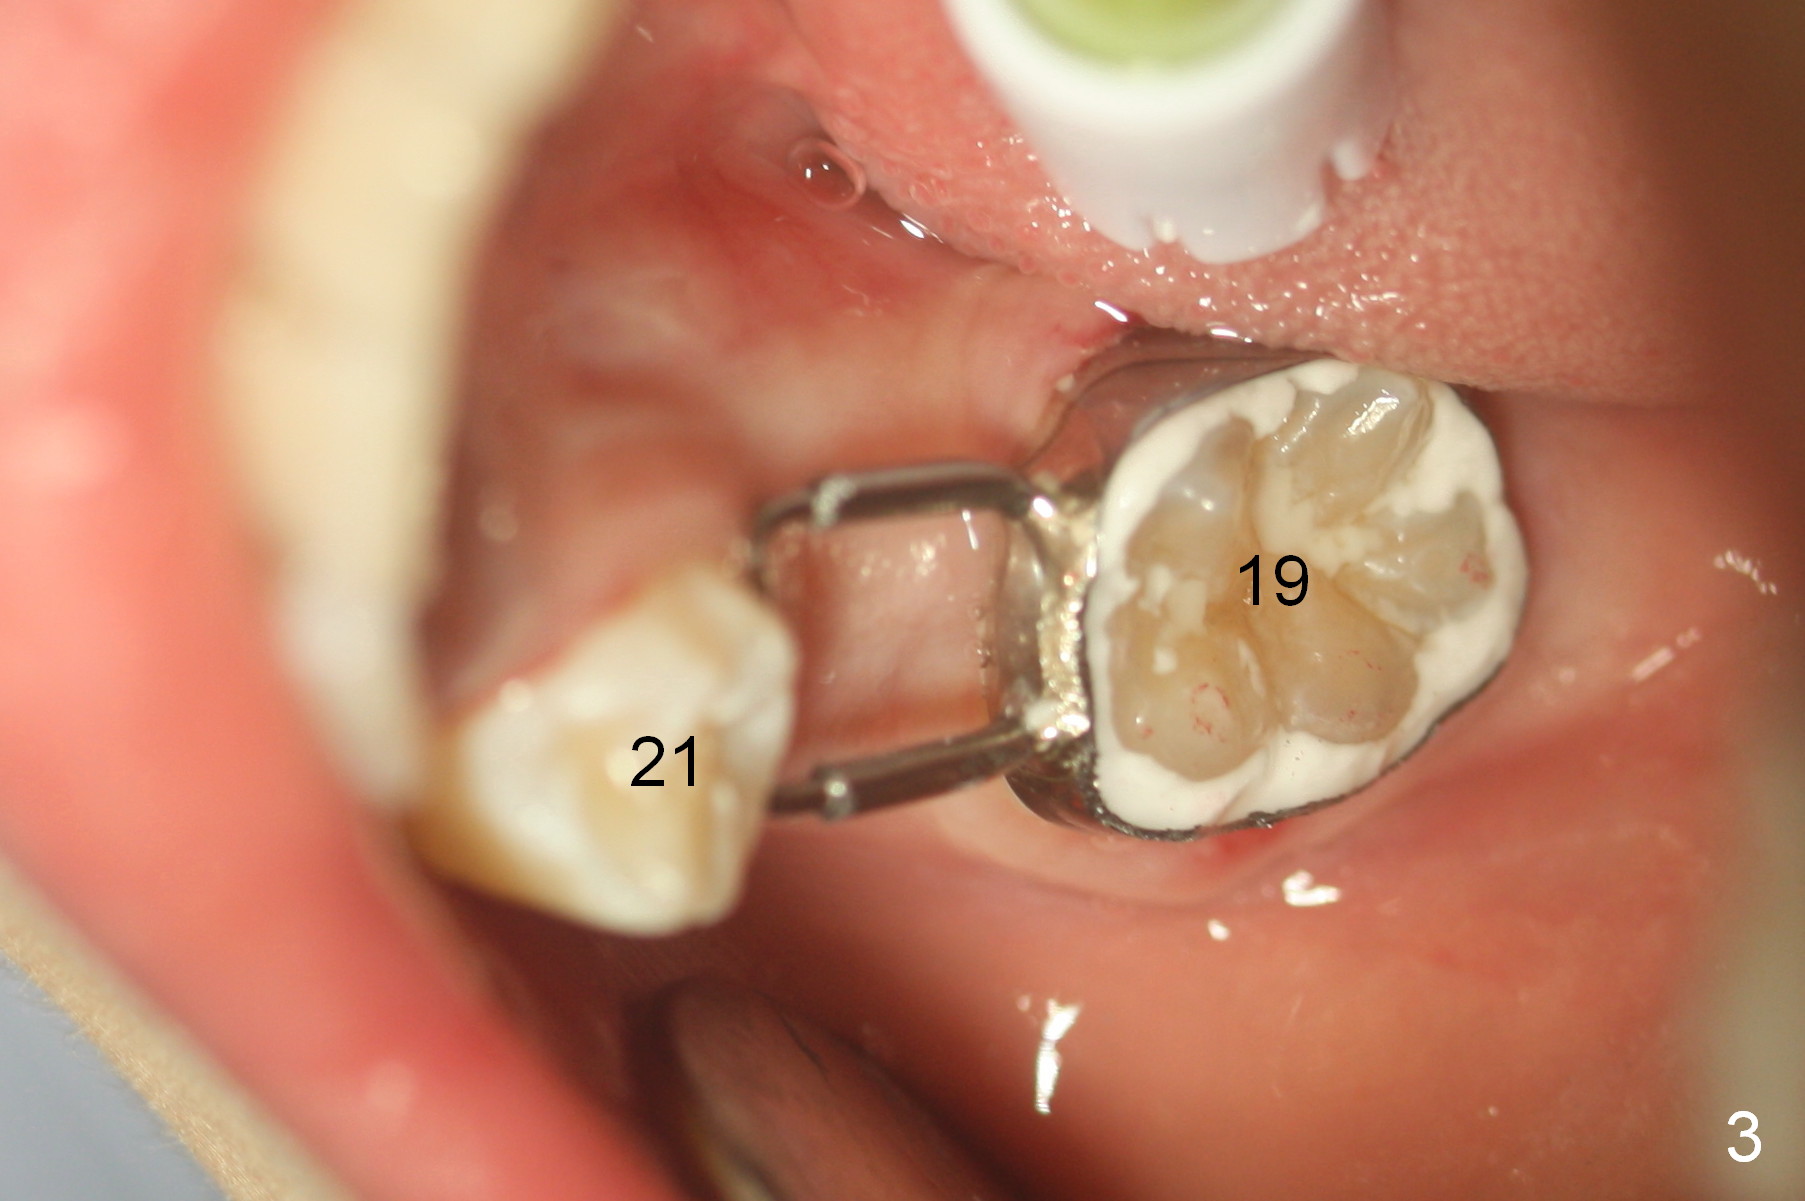

In 3 months, space has gained at J and T. Due to mobility of S, the space regainer is removed; a space maintenance is placed J (Fig.3 (9 years 4 months old)). The tooth #22 is erupting.